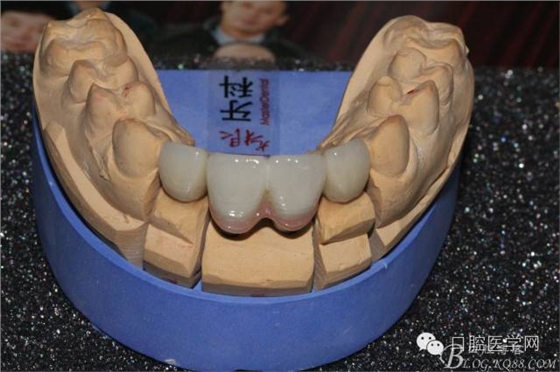

比色

因該患者笑線比較高,不微笑也露出牙齦,所以考慮到美觀,兩顆中切齒上方給做的牙齦瓷。